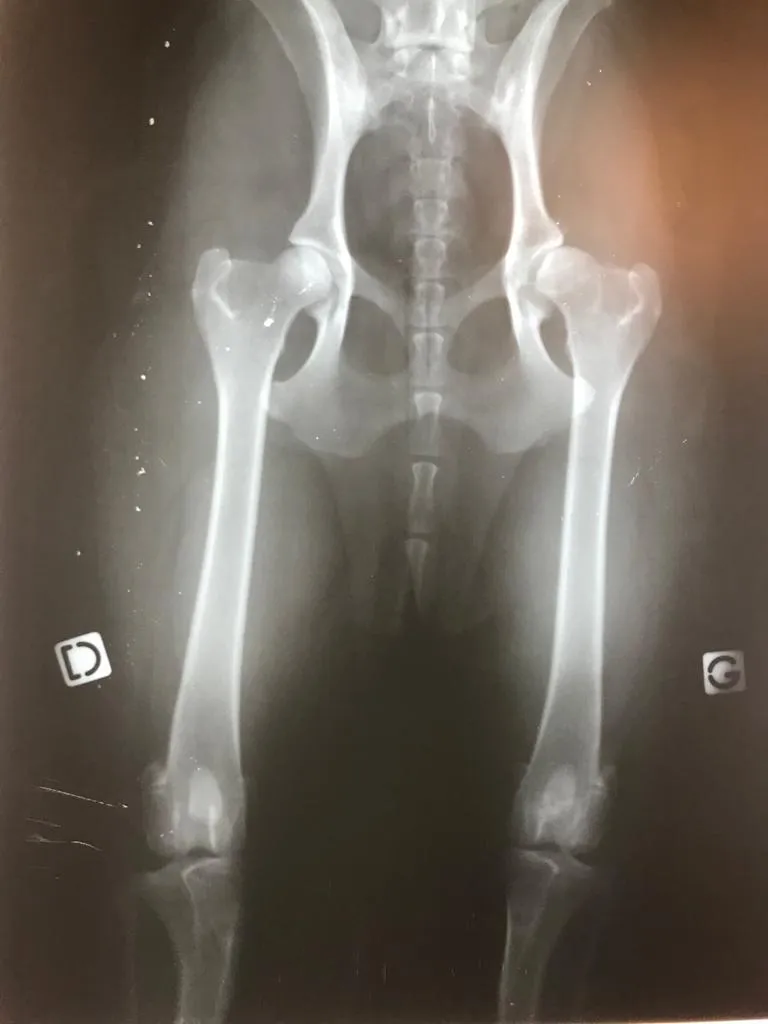

L’apparition de l’arthrose chez le chien survient souvent avec l’âge, mais parfois bien avant. Elle est assez fréquente et peut concerner des chiens jeunes, notamment après un traumatisme, une malformation ou une activité physique intense. Il faut apprendre à la détecter, à la faire diagnostiquer par un vétérinaire, puis à adapter le mode de vie du chien : son alimentation, son environnement et ses exercices. Il faut apprendre à la détecter, à la faire diagnostiquer par un vétérinaire, puis à adapter le mode de vie du chien : son alimentation, son environnement et ses exercices.